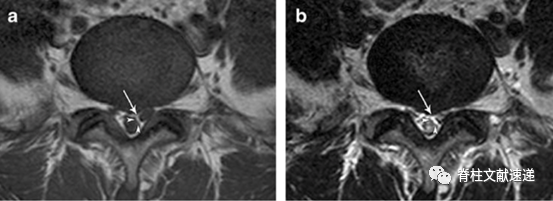

a.角形征(Corner sign):硬膜囊前外侧角的不对称形态;

b.新月形脂肪(Fat crescent sign):在异常神经根和硬膜之间存在月牙形硬膜外脂肪;

c.平行征(Parallel sign):异常神经根向椎间孔走形时可能非常平行于椎间盘,因此在椎间盘层面可见异常神经根的整个走形。

术中已经证实异常神经根。三角所示为角形征,双箭头所示为平行征(即异常神经根影)。